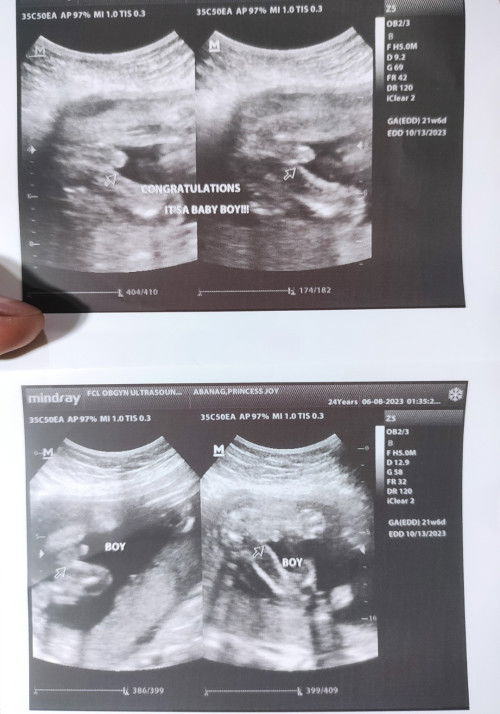

Share ko lang experience ko today mga mumsh☺️ Natatawa kasi ako sa sinabi nung sono na nag ultrasound samin ni baby sabi nya kasi grabe daw baby ko baby palang daks na ang putotoy kitang kita agad Haha hindi na daw sya nahirapan sa pagspot😂 HAHAHA cute eh sabi ko syempre kanino paba magmamana yan🤣✌️ Charr HAHA Iloveyou baby ko hindi kana little peanut, huling tvs ko liit liit mo pa ngayon laki laki mo na huhu excited na ako ma meet ka hindi pa alam ni dadi mo gender mo pero sure ako matutuwa yun sa gender reveal party mo☺️🩵 Mahal na mahal ka namin ni dadi mo stay healthy lang makakaraos din tayo😚 Godbless sa lahat ng mumsh dyan & congrats din po sa mga alam na ang gender at sa mga hindi pa hintay lang po kayo kasi sobrang sarap sa feeling maexperience to sa tamang weeks na sureball 100% na nila sasabihin ang gender at di mo na need bumalik promise.🥰❤️ #Genderreveal #21W6D #Babyboy